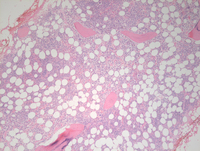

Bone marrow biopsy findings

Bone marrow biopsy demonstrated about 50-60% cellular marrow (otherwise almost normocellular for age) with evidence of an increased mononuclear blastic component percolating throughout the interstitium at higher power (image of the right side).